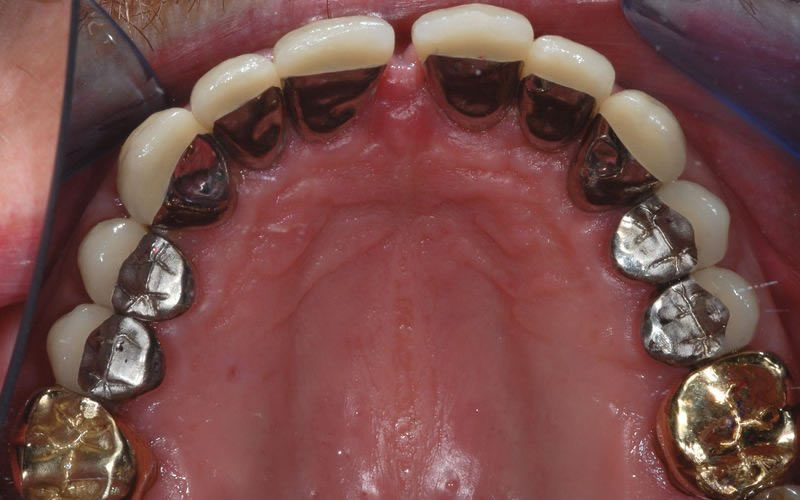

A Crown, also known as a Cap, can be made from porcelain or metal or a combination of both. They can also be made from gold.

Dental Crowns (7 images)